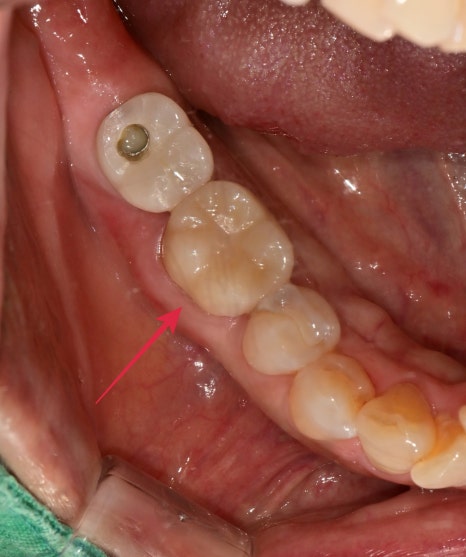

10개월이 지난 후 찍은 엑스레이 사진과 구내 사진입니다

증상은 치료 전과 비교했을 때 통증이나 불편감은 없으시다 하셨고

뿌리 주변의 염증소견도 나아진 상태입니다.

치료전 염증이 컸던 치아라 걱정하며 주기적으로 체크를 하는 중인데

다행히 잘 유지되고 있습니다.